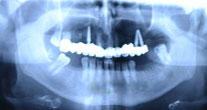

Oferim un pachet complet de servicii stomatologice in Jibou si nu numai: implanturi dentare, radioviziografie dentara, chirugie oro-dentara, terapie, proteica dentara, profilaxie, cosmetica dentara.Mai multe detalii ...